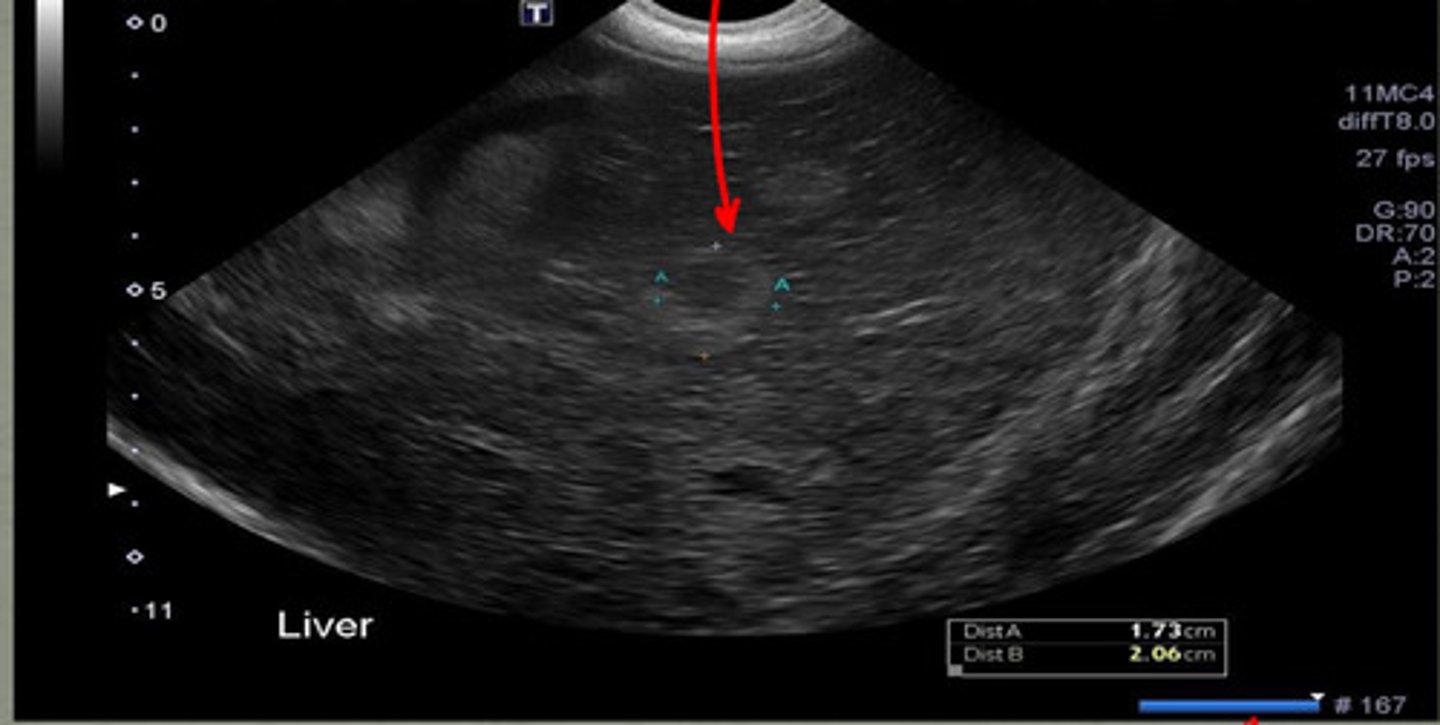

echogenicity- anechoic

shape- tear drop

how does the gallbladder appear on ultrasound? (echogenicity and shape)

the right side of the liver

where is the gallbladder located in respect to the liver?

1

the wall of the gallbladder is usually less than ____ mm in cats and dogs

anechoic

normal bile is what echogenicity?

biliary sludge or concretions

what is the echogenic material in the gallbladder?

gallbladder

if this US image was taken on the right side of the liver, what structure would this be?

distal enhancement

what artifact is the red circle indicating underneath the gallbladder?

-distal acoustic enhancement

-refraction

what are the two artifacts associated with the gallbladder?

increases echogenicity in liver parenchyma deep to gallbladder

what does distal acoustic enhancement do?

bending artifact at edges of gallbladder, seen at curved surfaces

what is refraction artifact?

star- distal enhancement

arrow- refraction

does the star or arrows show distal enhancement or refraction?